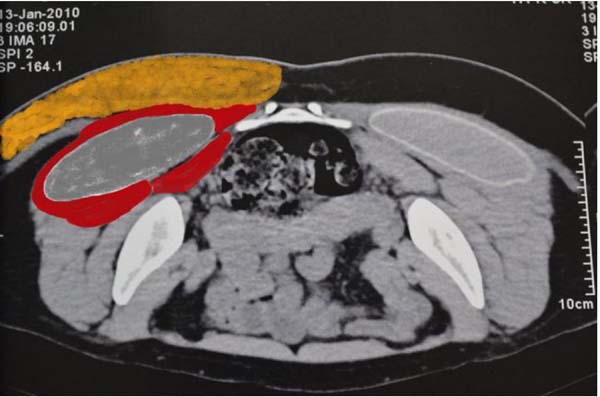

O deslocamento da prótese de sua loja intramuscular deve ser suspeitado durante o exame físico. A conduta, nesses casos, deve ser guiada pela tomografia computadorizada em decúbito ventral, onde se identifica o posicionamento da prótese glútea e é feita medida da espessura do músculo glúteo máximo da paciente (Figuras 3 e 4). Nos casos onde o músculo apresenta espessura maior que 2 cm, a resolução pode ser feita em um único tempo cirúrgico, onde se confecciona uma nova loja intramuscular. Naquelas pacientes onde o músculo glúteo máximo apresenta espessura menor que 2 cm, a correção deve ser feita em dois tempos cirúrgicos, sendo o primeiro para retirada da prótese glútea e um segundo tempo, realizado após um intervalo de 4 a 6 meses, no qual se confecciona uma nova loja intramuscular.